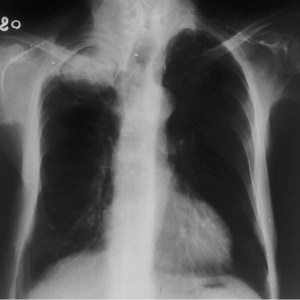

SIGNO DE LA GALAXIA Y SIGNO DEL CÚMULO SARCOIDEO

Se trata de dos signos de sarcoidosis visibles en la TC de tórax, en ventana de parénquima. El signo de la galaxia consiste en un nódulo mayor de un centímetro rodeado de pequeños nódulos satélites. El nódulo central está formado por granulomas confluentes y los pequeños nódulos periféricos son granulomas no confluentes. En la imagen superior vemos nódulos de distribución peribroncovascular y pueden verse nódulos de mayor tamaño rodeados por otros satélites de menor tamaño.

El signo del cúmulo sarcoideo corresponde a nodulillos centrolobulillares de muy pequeño tamaño, próximos pero no confluentes, formando un grupo o acúmulo en la periferia del pulmón que presenta una apariencia que recuerda a los cúmulos de estrellas.

A diferencia del signo de la galaxia sarcoidea, no hay un nódulo central de mayor tamaño. En la imagen se muestra este signo.